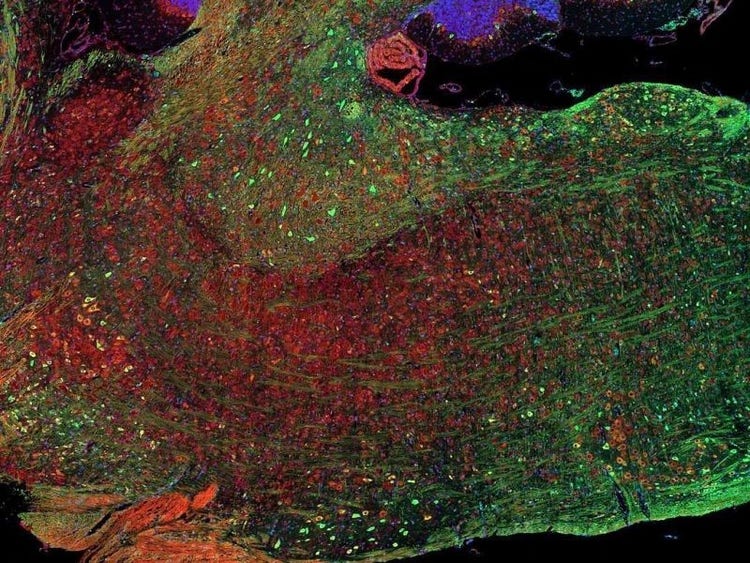

Fluorescence imaging of a mouse brain

Aunque todas estas imágenes parecen distintas en un primer plano, todas componen una única imagen de un cerebro de ratón capturada con el procesamiento de imágenes por fluorescencia.

El científico británico Sir George G. Stokes observó por primera vez que la fluorita mineral mostraba fluorescencia al iluminarla con luz ultravioleta y acuñó la palabra "fluorescencia". Stokes descubrió que la luz de fluorescencia tiene longitudes de onda más largas que la luz de excitación, un fenómeno conocido como cambio de Stokes. La microscopía por fluorescencia es un método excelente para estudiar materiales que pueden fluorecer en su forma natural (calificado como primaria o autofluorescencia) o cuando se tratan con químicos que puedan fluorecer (conocido como fluorescencia secundaria).